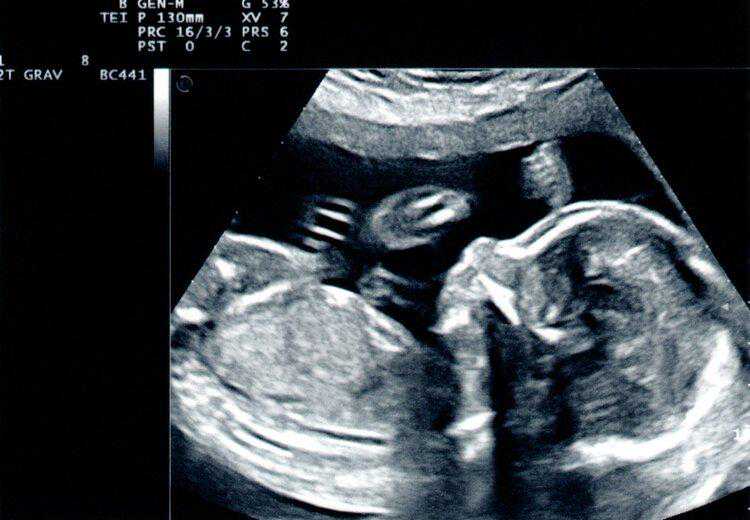

全面揭示试管婴儿的全过程,送给每一位渴望称为母亲的女人

当然不是,事实上是取出妈妈的卵子和爸爸的精子,在体外通过科学...

做试管婴儿全过程,每一步都很艰难,看着都疼,母亲实在太伟大

孩子,是两个人爱情的结晶,是每个家庭的期盼。但有一些人并不是...